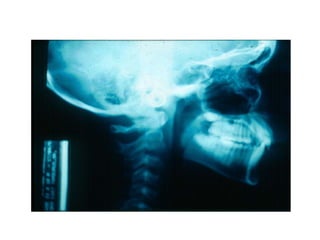

TRANSPOSIÇÃO TOTAL - CANINO COM INCISIVO LATERAL MANOBRAS PARA CORREÇÃO DA ROTA DE ERUPÇÃO